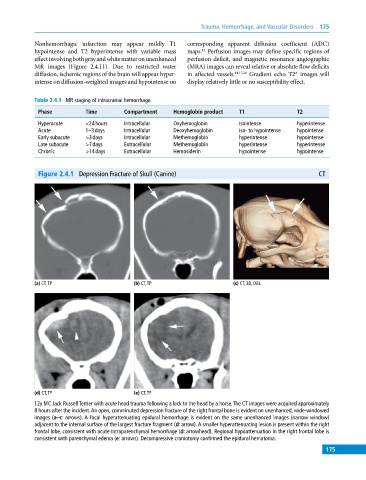

Figure 2.4.1 Depression Fracture of Skull (Canine) CT

(a) CT, TP (b) CT, TP (c) CT, 3D, OBL

(d) CT, TP (e) CT, TP

12y MC Jack Russell Terrier with acute head trauma following a kick to the head by a horse. The CT images were acquired approximately

8 hours after the incident. An open, comminuted depression fracture of the right frontal bone is evident on unenhanced, wide‐windowed

images (a–c: arrows). A focal hyperattenuating epidural hemorrhage is evident on the same unenhanced images (narrow window)

adjacent to the internal surface of the largest fracture fragment (d: arrow). A smaller hyperattenuating lesion is present within the right

frontal lobe, consistent with acute intraparenchymal hemorrhage (d: arrowhead). Regional hypoattenuation in the right frontal lobe is

consistent with parenchymal edema (e: arrows). Decompressive craniotomy confirmed the epidural hematoma.